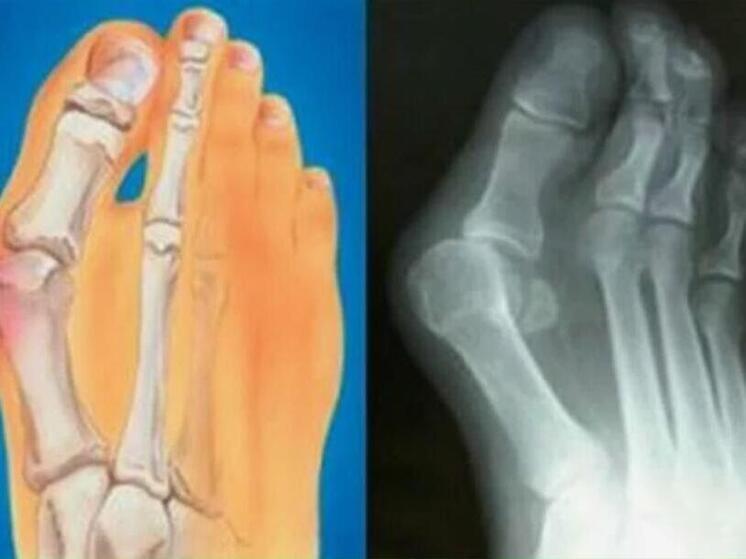

Многим знакома проблема болезненной «шишки» у основания большого пальца стопы. Она мешает ходить, портит обувь и со временем вызывает постоянную боль. Как объяснил травматолог-ортопед ММЦ имени Н. И. Пирогова ФМБА России Виктор Самодолов, причина кроется не в самой «косточке», а в вальгусной деформации стопы.

При этой патологии стопа распластывается, первый палец отклоняется в сторону, а организм формирует костное разрастание для дополнительной опоры. Ранее проблему связывали с каблуками и нагрузками, однако сегодня доказано, что чаще всего она обусловлена наследственностью и передается по женской линии.